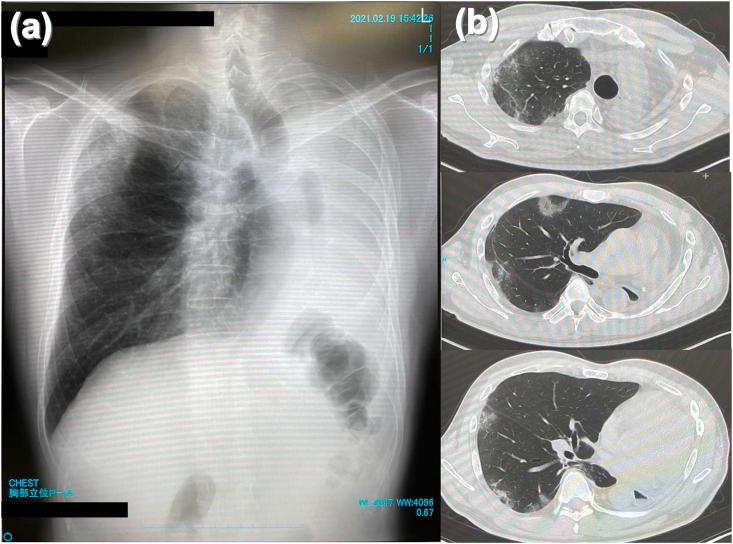

Eosinophils play an important pathogenetic role in the development of eosinophilic granulomatosis with polyangiitis (EGPA). EGPA has long been treated with systemic corticosteroids and immunosuppressive agents. However, in recent years, biologic agents targeting eosinophils (-IL-5 antibody; mepolizumab) have also been used. Evidence regarding the effectiveness of using benralizumab, -IL-5 receptor α monoclonal antibody that depletes eosinophils via antibody-dependent cell-mediated cytotoxicity, has been growing. Benralizumab is used as a steroid-sparing treatment option for EGPA. Clinical studies have evaluated the effects of using mepolizumab or benralizumab in combination with steroids for the treatment of EGPA. However, to date, there have been no reports of using biologics alone. Herein, we describe the case of a patient with active EGPA refractory to benralizumab monotherapy. The patient achieved significant improvement in symptoms after administration of corticosteroids during hospitalization. Benralizumab monotherapy might not be considered a therapeutic option for patients with active EGPA in whom corticosteroids are initially indicated.

嗜酸性粒细胞在嗜酸性肉芽肿性多血管炎(EGPA)的发病机制中起重要作用。长期以来,EGPA一直采用全身糖皮质激素和免疫抑制剂治疗。然而,近年来,靶向嗜酸性粒细胞的生物制剂(抗IL-5抗体;美泊利单抗)也被使用。关于使用贝那利珠单抗(一种通过抗体依赖性细胞介导的细胞毒性作用消耗嗜酸性粒细胞的抗IL-5受体α单克隆抗体)有效性的证据越来越多。贝那利珠单抗被用作EGPA的一种减少激素用量的治疗选择。临床研究评估了美泊利单抗或贝那利珠单抗与糖皮质激素联合用于治疗EGPA的效果。然而,迄今为止,尚无单独使用生物制剂的报道。在此,我们描述了一例对贝那利珠单抗单药治疗难治的活动性EGPA患者的病例。该患者住院期间给予糖皮质激素治疗后症状有显著改善。对于最初需要使用糖皮质激素的活动性EGPA患者,贝那利珠单抗单药治疗可能不是一个治疗选择。